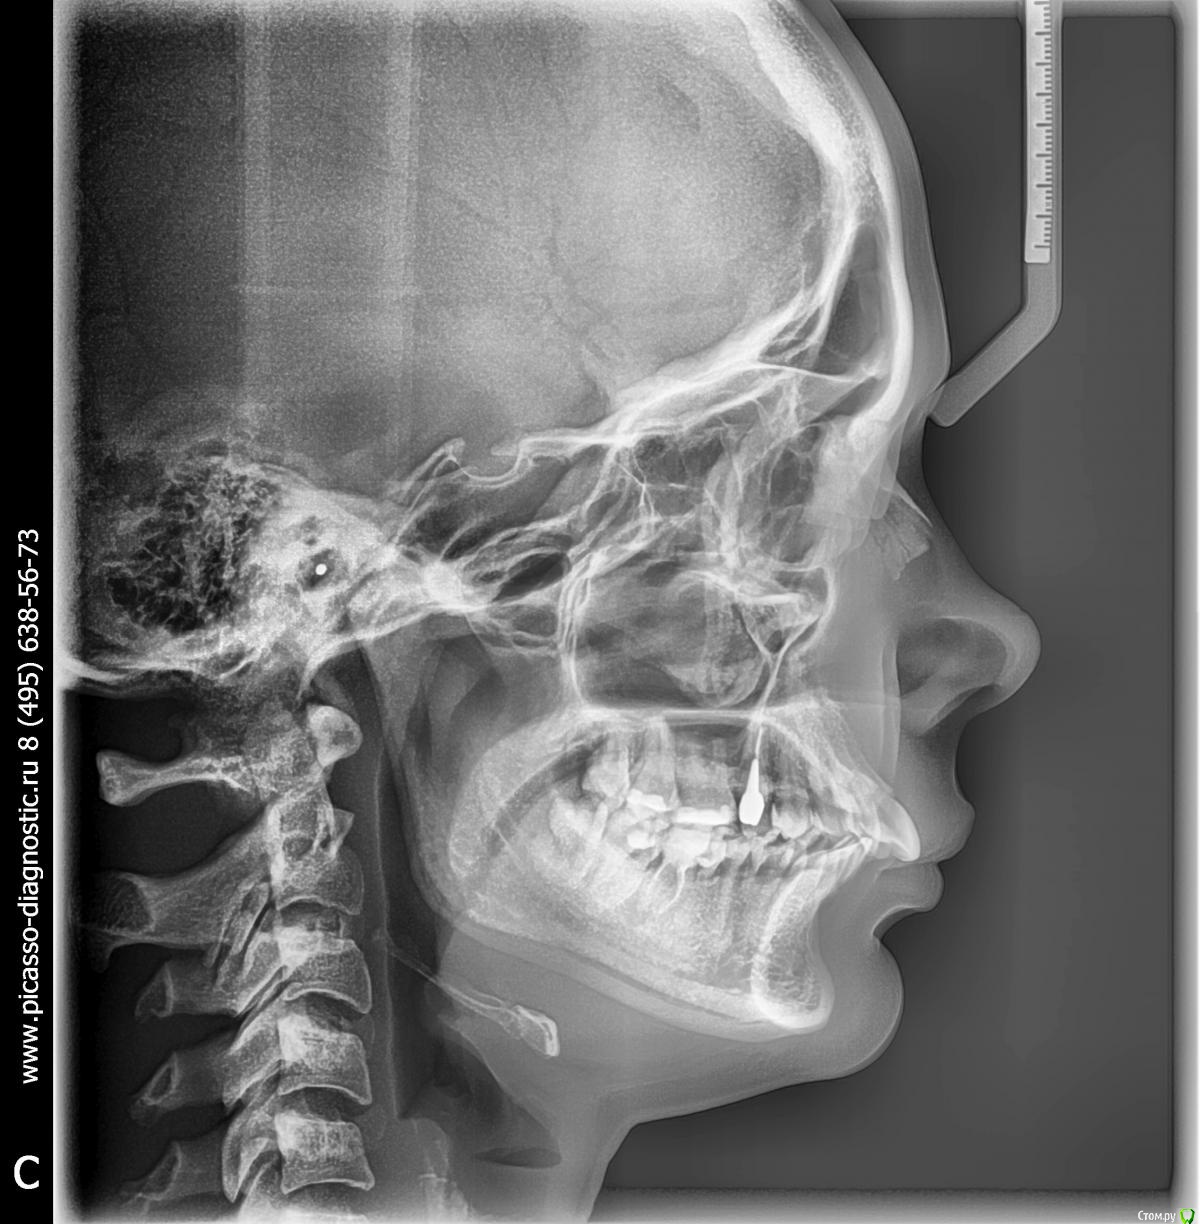

Необходимо сделать ОПТГ в прикусе (при всех сомкнутых зубах) или кт височно-нижнечелюстного сустава. Тогда будет понимание о смещении/положении самой нижней челюсти.

По Трг Вам однозначно необходимо удаление зубов на в.ч, а возможно и на н.ч т.к очень сильный наклон передних зубов.

По поводу ортохирургии вопрос неоднозначный и зависит от Ваших эстетических требований. Учитывая что они у Вас не запредельные, то я бы от серьезно задумался по поводу хирургии.